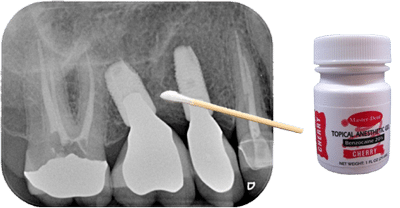

The Q-tip test involves gently touching or applying light pressure to areas of the face or oral tissue with a cotton swab (Q-tip) to determine whether the contact reproduces the patient’s pain. Because neuropathic pain is often triggered by light touch or pressure, this assessment can provide important clues about the nerve involvement in a patient’s symptoms.

- Light touch assessment: Gently stroke the reported area with a Q-tip, as if you were using a paintbrush with a light touch, to see if this elicits the familiar pain.

- Firm pressure assessment: Apply gentle, firm pressure on several areas around the painful site with the Q-tip to see if deeper mechanoreceptors trigger the pain.

- Anesthetic verification: If pain is replicated, a topical anesthetic such as 20% benzocaine can be applied to the area. Wait a few minutes and repeat the test. A reduction or elimination of pain supports the diagnosis of neuropathic pain.